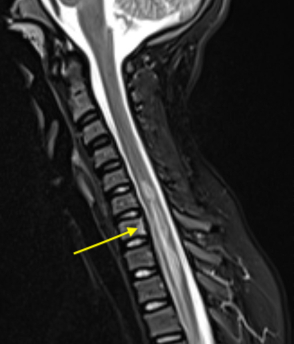

Results: An 11yo F presented with sudden onset back pain and lower extremity sensory disturbances following an ATV ride that quickly evolved into an ascending paralysis with associated urinary retention. Exam showed 4/5 strength in proximal UEs, 2/5 grip strength on the right, and 0/5 strength in LEs with associated areflexia and decreased sensation to light touch and pinprick but preserved vibratory sense. CSF studies were unremarkable with no albuminocytologic dissociation or lymphocytic pleocytosis. EMG/NCS revealed absent F-waves consistent with possible early demyelinating polyradiculopathy. She was started on IVIG given concern for AIDP. Extensive work-up including TSH, ESR, CRP, B1, B12, heavy metals, C. jejuni Ag, stool cx, blood cx, ANCA vasculitis panel, RMSF and Arbovirus Abs, and AchR and MuSK Abs was unremarkable. MRI revealed diffusion restriction in the cervicothoracic cord without enhancement (Fig 1). She had no improvement of her symptoms after completing 5 days of IVIG. She also developed long-tract signs including +Babinski on the left and LE spasticity. Repeat imaging 4 days from prior revealed adjacent vertebral body with area of T2 hyperintensity concerning for bony infarct (Fig 2). Given her rapid onset of symptoms, lack of improvement after treatment with IVIG, and development of long-tract signs, she was given a diagnosis of spinal cord infarction. FCE was deemed the etiology given the presence of adjacent bony infarct suggesting embolic phenomenon and the lack of evidence of CNS inflammation, infection, or other etiology. Repeat EMG/NCS showed evidence of severe reduction in the amplitudes of the compound motor action potentials which can be seen in compromise of the motor neuron population due to spinal cord infarction (Fig 3). She was discharged to inpatient rehab.